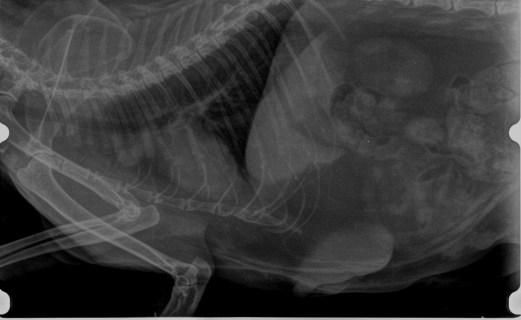

TUMORES DE MAMA EN GATAS: Prevención, detección y tratamiento